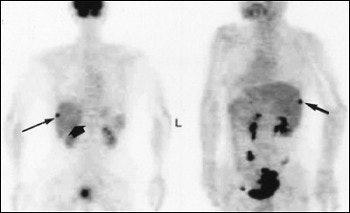

A 62-year-old woman with heterogeneous cyst of the liver. Abdominal CT scan (above) shows heterogeneous cystic lesion with suspected parenchymal liver metastasis (arrow), but not peritoneal implants on liver surface. Whole-body FDG-PET (below) scan in maximum intensity projection does not indicate significant FDG uptake in liver parenchyma (thin arrows) beside hot spot at liver surface (thick arrow). Yoshida Y, Kurokawa T, Kawahara K, Tsuchida T, Okazawa H, Fujibasyashi Y, Yonekura Y, Kotsuji F, "Incremental Benefits of FDG Positron Emission Tomography over CT Alone for the Preoperative Staging of Ovarian Cancer," (AJR, January 2004, Vol.182, pp. 227-233).